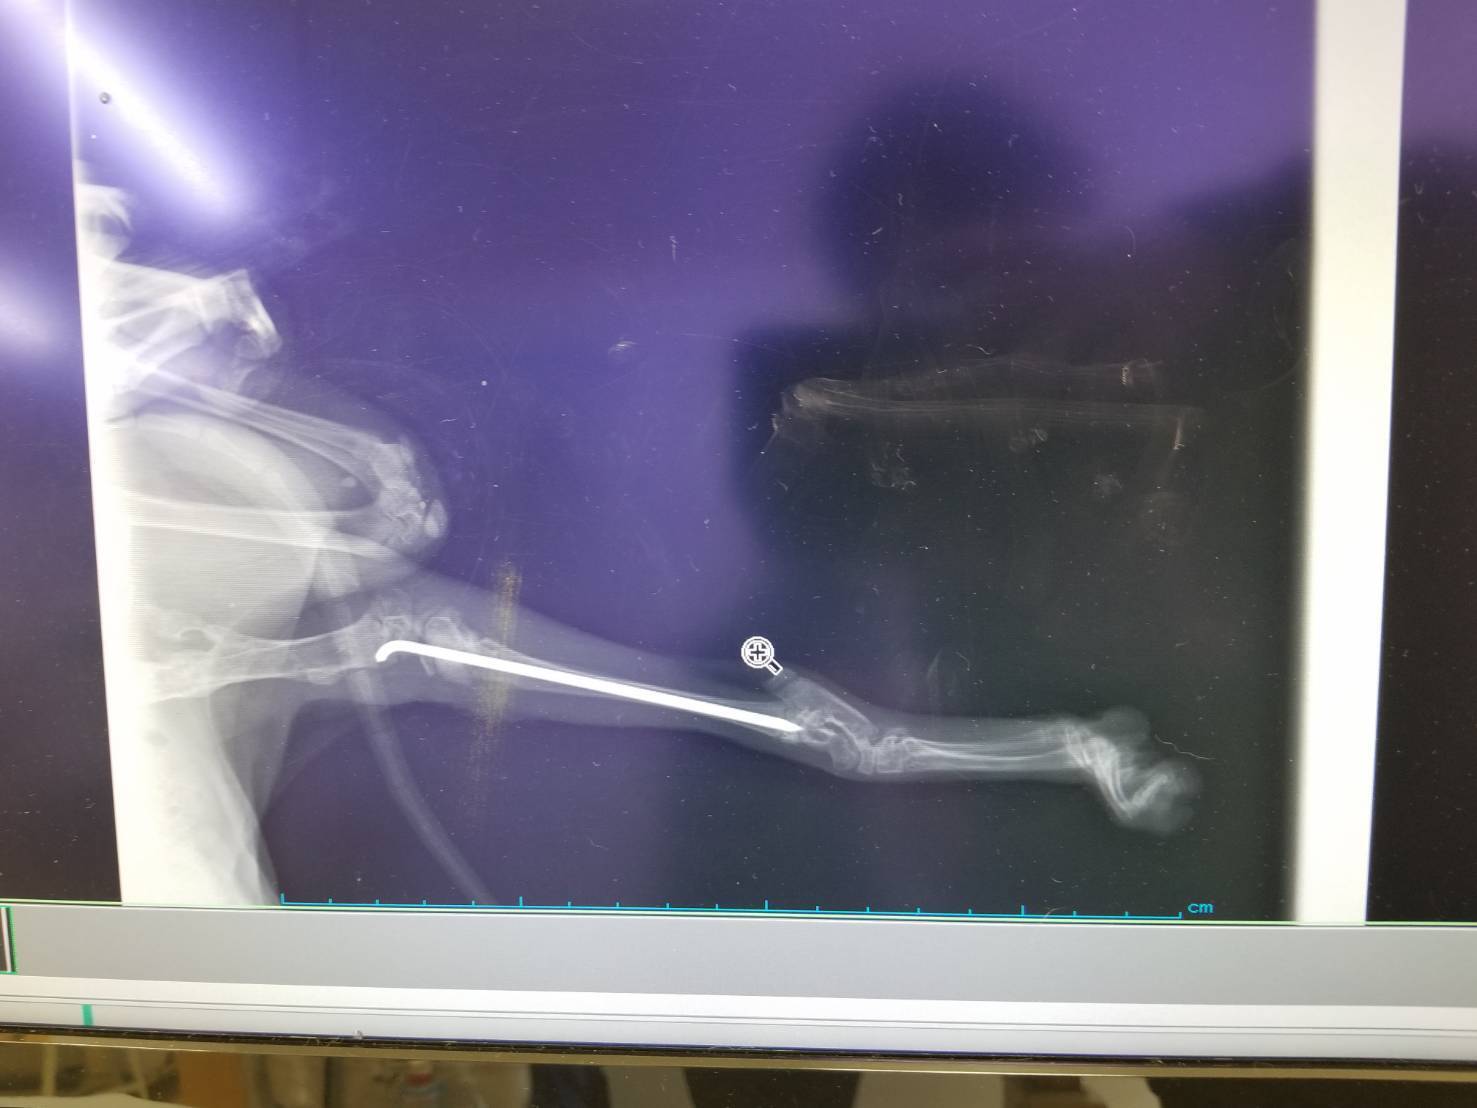

今回の手術で一本ピンが留置されていますがこちらは話し合いの結果、抜去の必要がない可能性が高いため、去勢手術の際に様子を見て必要なら行うこととなりました。